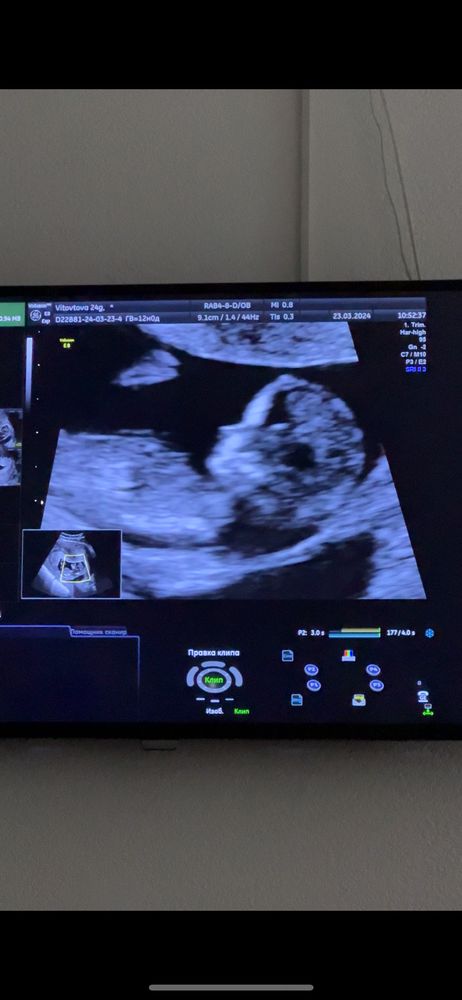

1 СКРИНИНГ ❤️ девчонка 80% носик мой☺️

Bee, по видео у меня везде зернышко 🤞🏻☺️

Dina, не спорю что на писюн похоже🤣 только в обратную сторону🤣 а вообще там кофейное зернышко, просто скриншот такой🫠